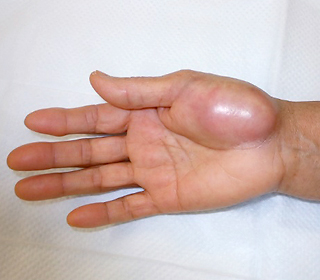

骨腫瘍は病的骨折(病気が進行し骨が折れてしまうこと)などによる痛みで気づくことが多いですが、症状がなくても検診などで偶然みつかることもあります。軟部腫瘍は痛みのないしこりとして気づくことが多く、進行して大きくなってから受診されることが多くあります。ほとんどの悪性腫瘍は痛みがなく、また小さい腫瘍でも悪性のことがあるため、放置せずに早目に病院を受診されることをお勧めします。